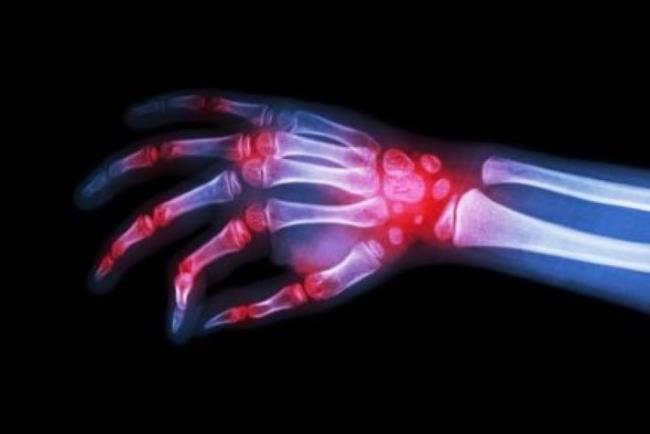

טוקיליזומאב (Tocilizumab) היא תרופה ביולוגית לטיפול בדלקת פרקים ראומטית ובמחלת systemic juvenile idiopathic arthritis.

IL6 הוא ציטוקין אשר מעורר תגובה דלקתית אשר מתבטאת בין היתר בכאבי פרקים, נפיחות ותסמינים נוספים. חסימת התפקוד של IL6 על ידי שימוש בTocilizumab הוכחה כיעילה מאוד בטיפול במחלות האלה ויכולה לשפר באופן משמעותי את איכות חייהם של החולים.

התרופה הראתה האטת נזק לסחוס ולעצם במפרקים, הנגרם על-ידי המחלה וכן הראתה שיפור ביכולת לבצע משימות יומיות בצורה תקינה. ניתנת בדרך כלל בשילוב עם מטוטרקסט. אולם, ייתכן שתינתן לבד.

צילום רנטגן